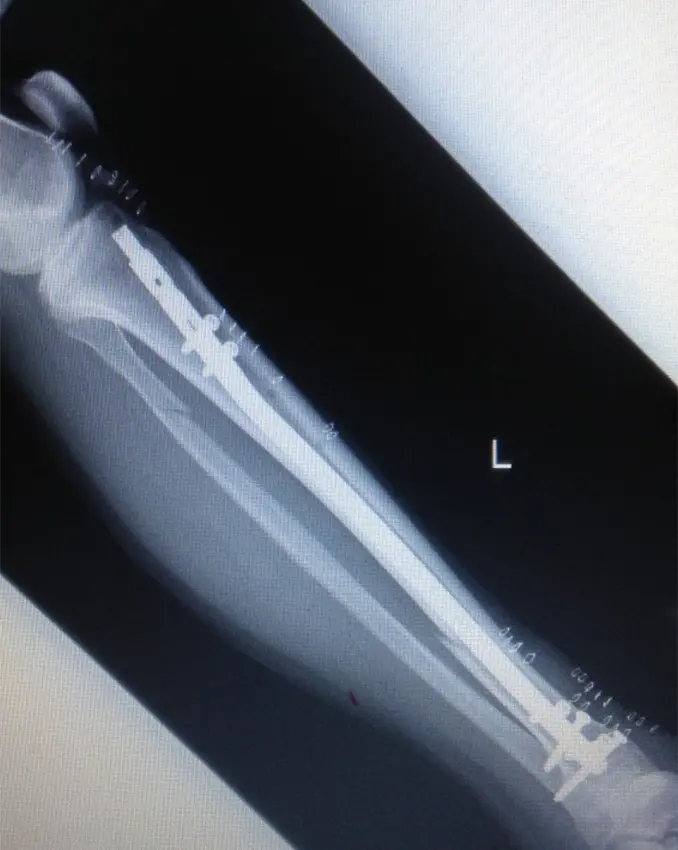

患肢の腫脹が改善し、血糖コントロールがついたところで、受傷17日目に観血的整復固定術(手術時間:90分)を施行した。

ターニケット未使用、体位は仰臥位で膝関節軽度屈曲位にて手術を行った。皮切は外側関節裂隙から膝蓋骨関節縁とした。外側膝蓋支帯を切開、膝蓋腱および関節包の間を剥離、ガイドピン刺入部を露出した。ガイドピンを刺入し、ドリリングした後、ガイドワイヤーを挿入。遠位骨片にブロッキングピン刺入後、徒手的に整復しながら径12.5mmまでリーミングし、径11mm、長315mmのSynthes社製 Expert Tibial nailを挿入した。近位はスクリュー2本、遠位スクリュー4本挿入固定とした。固定性良好であることを確認し、エンドキャップを挿入、洗浄閉創し手術終了とした。

(図4)術後単純X線